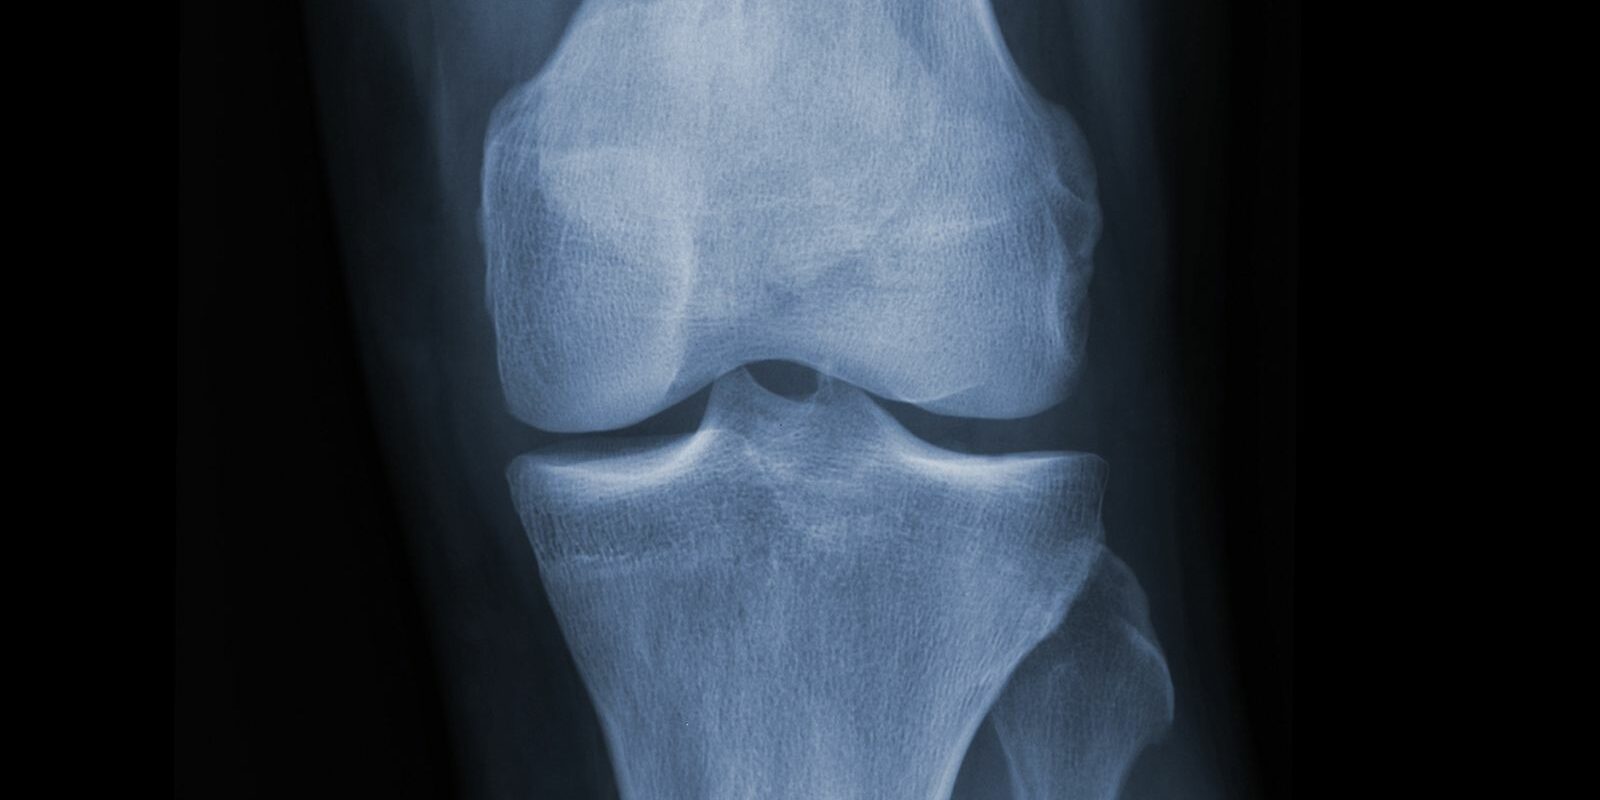

Vitamin D Bone Density Scan . Researchers gave more than 300 healthy adults daily doses of 400 international units (iu), 4,000 iu, or 10,000 iu of supplemental vitamin d. Calcium and vitamin d are important for keeping bones strong and helping to prevent osteoporosis. Osteoporosis is a common bone. A bone density test is a measurement of how much mineral, such as calcium, you have in your bones. The most common and most versatile test. It can be used to test for osteoporosis or to take a closer look at body composition.